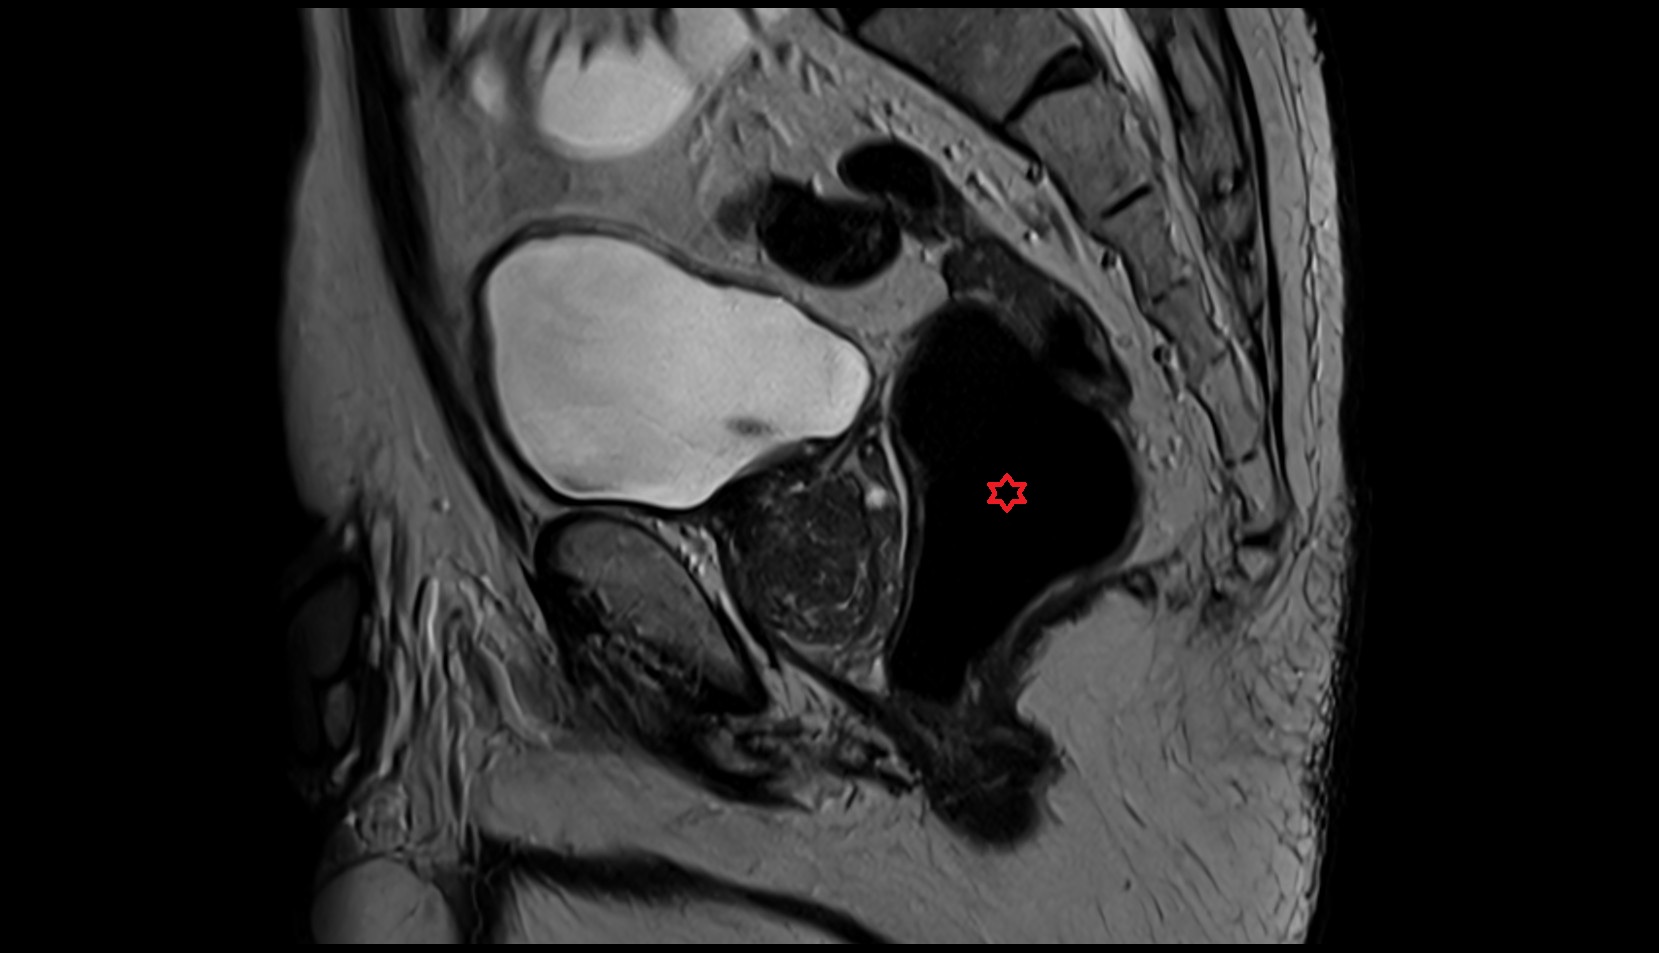

- Uterus

- Body of uterus

- Fundus of uterus

- Cervix of uterus

- Isthmus of uterus

- Vagina

- Fornix of the vagina

- Endometrium of uterus

- Myometrium of uterus

- Perimetrium of uterus

- Junctional zone of uterus

- Vesicouterine pouch

- Rectouterine pouch (pouch of Douglas)